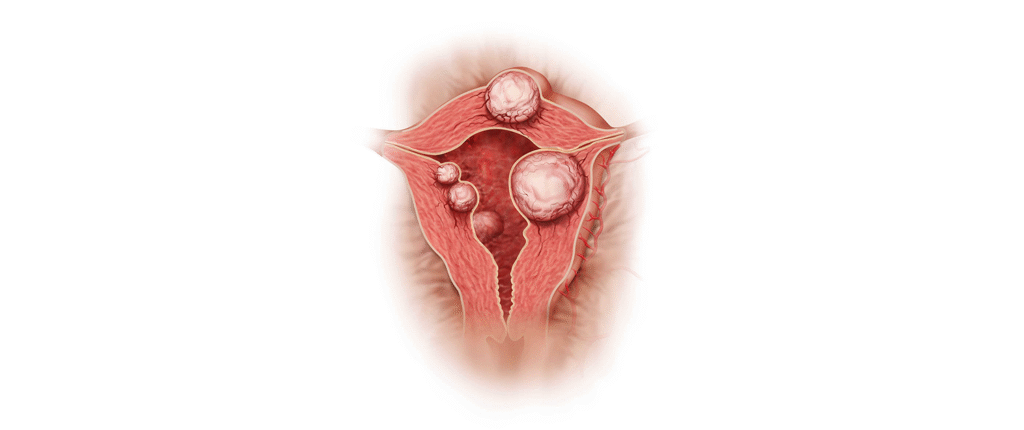

Myomlar (Rahim Urları)

Myomlar, doğurganlık çağında ki kadınlarda görülen kanseröz olmayan yapılardır. Halk arasında ‘rahimde ur’ olarak da bilinirler. Neredeyse her 4 kadından 3’ünde myom gelişir, ancak genellikle herhangi bir şikayete neden olmadıklardan çoğu kişi myomlarının varlığından habersizdir. Myomlar, sıklıkla rutin kontrol sırasında pelvik muayene ya da ultrasonografi ile tespit edilirler. Myomların neden oluştukları tam olarak tespit edilememiş olsa bile genetik faktör, obezite ve doğurgan yaşta olmak bilinen en büyük risk faktörleridir.

Myomların klinik bulguları genellikle lokalizasyonları ile ilişkilidir. Rahim kavitesinin içine doğru büyüyen submüköz myomlar, uzamış ve ağır kanamaya neden olurlar. Bu myomlar aynı zamanda gebe kalmak isteyen kadınlarda da problem yaratırlar. Subseröz myomlar ise rahimin dış kısmına doğru büyüyen myomlardır. Bazen mesaneye bası yaparak idrar ile ilgili şikayetlere neden olabilirler. Eğer rahmin arka tarafına doğru büyürlerse rektuma bası ile kabızlık, spinal sinirlere bası ile bel ağrısına neden olabilirler.

Myomlar, genellikle tedavi gerektirmezler fakat hastada aşırı kanama, anemi, ağrı ya da gebeliğe engel durum oluşturuyorlarsa cerrahi olarak çıkarılmaları gerekir.